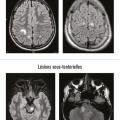

Diagnostics différentiels de la sclérose en plaques

Depuis 2001 et la première version des critères « contemporains » de sclérose en plaques (SEP), les connaissances épidémio­logiques et physiopathologiques de la maladie se sont considérablement étoffées, et les progrès en imagerie sont majeurs.1 Cependant, malgré ces avancées remarquables, le diagnostic de SEP reste parfois…